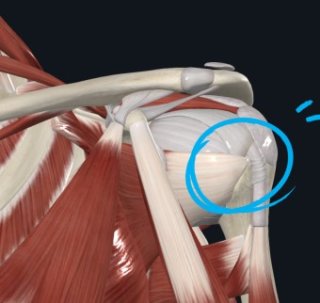

1. 어깨통증 원인 - 회전근개 파열(어깨힘줄 손상)

가장 흔한 어깨통증 원인은 회전근개 손상입니다. 회전근개는 어깨를 안정적으로 움직이게 하는 네 개의 근육(극상근, 극하근, 견갑하근, 소원근)으로 이루어져 있습니다.

이 근육 중 하나라도 손상되면 팔을 들 때 통증이 생기고, 팔을 내릴 때 찌릿한 통증이 이어집니다. 특히 팔을 90도 이상 들어 올릴 때 통증이 심하고, 밤에 통증이 심해져 수면을 방해하기도 합니다.

나이가 들수록 힘줄이 약해지고, 반복적인 어깨 사용이나 갑작스러운 충격으로 인해 파열이 쉽게 생깁니다. 회전근개 파열은 단순 근육통과 달리 방치하면 힘이 빠지고 어깨 관절이 굳는 등 회복이 어려워질 수 있습니다.